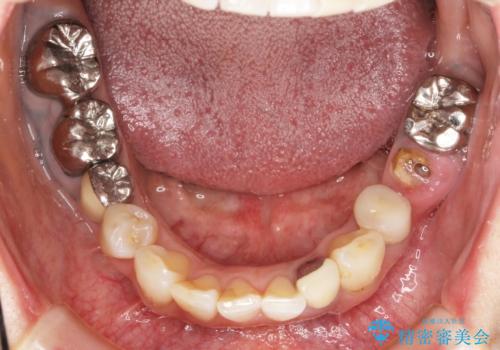

全顎的 虫歯治療 インプラント補綴

- 「他院で虫歯治療を行っているが、延々終わらず数年経過している。全体的な治療を希望したい。」と全顎的な治療を希望され来院されました。

・再発した虫歯

・銀歯の下にできた虫歯

・根尖性歯周炎

・残根状態の歯

など、虫歯を原因とする問題が多発した状態です。

今後延々と治療を繰り返さないために、全ての銀歯を外し虫歯を丁寧に取り切り、根管治療を行い、残せない歯は抜去を行った上でインプラント治療を行っていくことで全体的な治療を計画していくこととなりました。